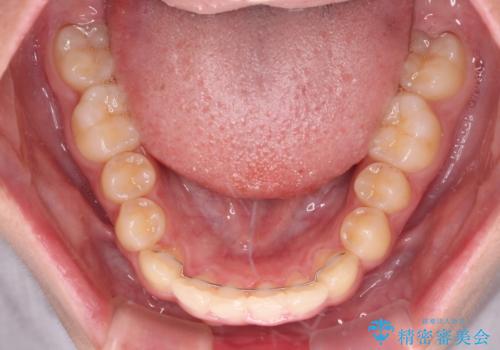

下の前歯が隠れてしまうほど深い咬み合わせ 高校生のインビザライン矯正治療

- 前歯の叢生と深い咬み合わせを気にして来院された患者様です。

奥歯の咬み合わせを見ると、上顎が下顎に対して相対的に前方にありました。

深い咬み合わせを改善するためには、上顎臼歯を後方に移動させつつ、下顎の小臼歯を直立させる必要があります。

インビザライン単体で対応ることも検討できますが、達成する可能性が低いため、カリエールディスタライザーという補助装置を併用して、より確実性を上げることとしました。

奥歯の咬み合わせと深い咬み合わせを改善した後、インビザラインで歯列を整えることとしました。